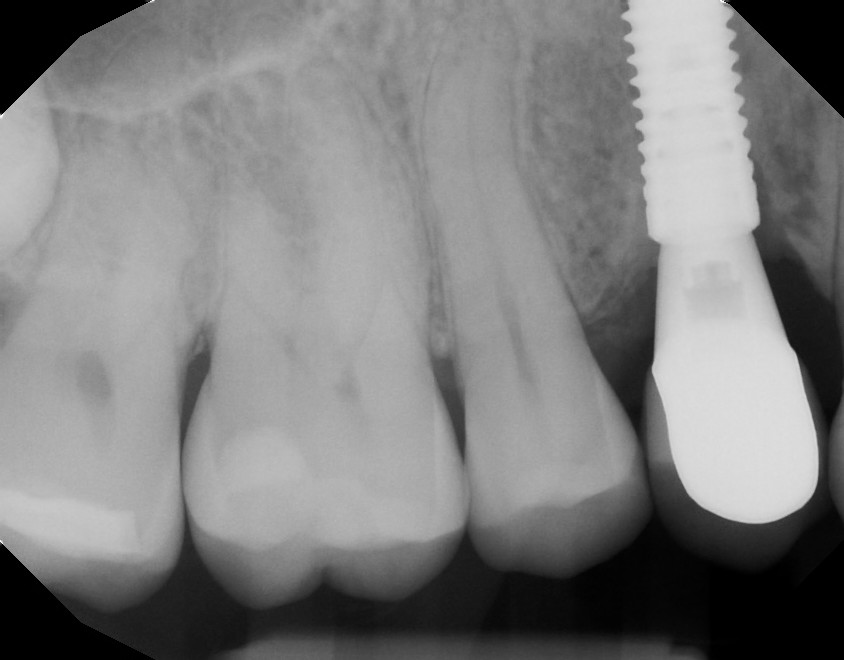

This mouth had recession on just one tooth with very little bone to support the tooth. The area needed support and thickness. The tissue was placed and the area now has thicker tissue to withstand the forces that the patient needs to place on it.